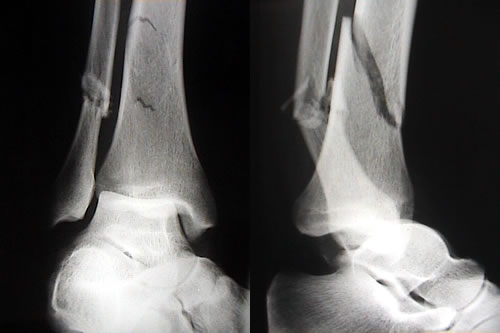

Investigadores Argentinos comprueban que la enfermedad celíaca aumenta el riesgo de fracturas

Algunos estudios científicos sugieren que si la enfermedad celíaca no está diagnosticada y tratada quienes la padecen tienen mayores riesgos de sufrir fracturas. Una nueva investigación –publicada en la revista...